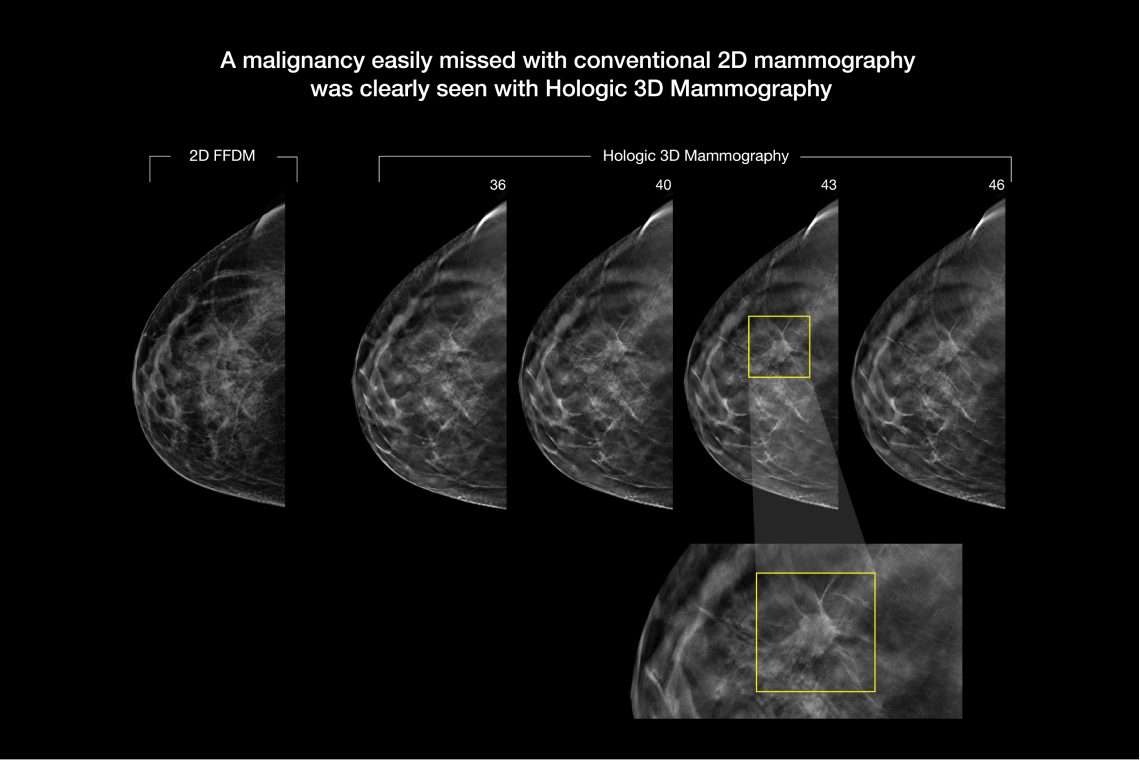

- Proven to detect 20%-65% more invasive breast cancers compared to 2D alone, an average increase of 41%.1

- FDA approved as superior for women with dense breasts compared to 2D alone.2,4